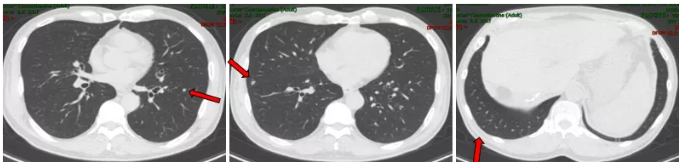

2017.12 复查提示CEA 16.16 ng/ml,CA 125 111.2 u/ml,肺部CT提示双肺及叶间裂胸膜处多发小结节。

肺部CT检查

影像学检查